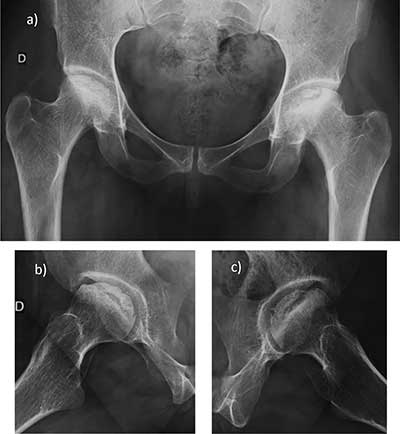

Figure 4

Stress fractures of the sacrum postpartum. Transversal T1 a), STIR b), and coronal T2 c) Images show two thin fractures lines, of low T1 and high T2 signal, located at 1–2 cm of the sacroiliac joints (arrows) and associated with bone marrow edema.